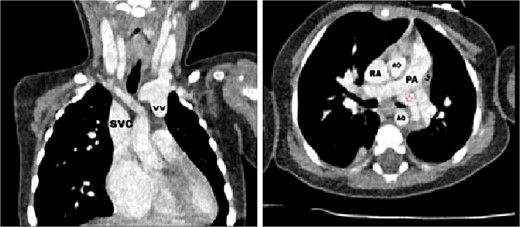

Transthoracic echocardiography (TTE) revealed an isolated supracardiac type of TAPVC, accompanied by a large ostium secundum atrial septal defect (ASD) measuring 9 mm, exhibiting a right-to-left shunt. Furthermore, there was evidence of dilatation in the right heart cavities and severe pulmonary hypertension (PHT = 65 mmHg). The common pulmonary confluence, measuring 12 mm in diameter, drained into the left innominate vein via a vertical vein. Confirmatory computed tomographic angiography (CTA) supported the diagnosis of supracardiac type TAPVC and identified stenosis along the venous pathway between the right and left pulmonary veins (Figs 1 and 2).

Axial (right) and coronal (left) postcontrast computed tomography sections: SVC: superior vena cava, VV: vertical vein, RA: right atrium, LA: left atrium, AO: aorta, PA: pulmonary artery, red star: The confluence of PVs.

CT scan showing the right pulmonary veins (RPVs) and left pulmonary veins (LPVs) join all together posterior to the left atrium (LA) and pulmonary artery (PA), also showing the stenosis within the venous confluence between the drain of the right pulmonary veins and the drain of the left pulmonary veins.